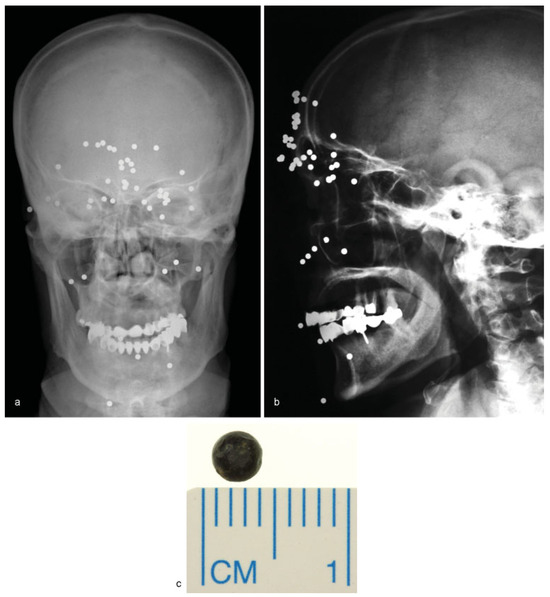

• Case 3: A 64-year-old patient shot himself by accident while handling a self-made rat trap in Turkey. Four days later, the patient travelled back to Germany on his own and visited the emergency department. Aside from multiple skin lesions, mainly around the periorbital region, clinical examination including ophthalmological assessment was uneventful, with the patient reporting only slightly blurred vision. Conventional X-ray demonstrated the presence of multiple shotgun projectiles throughout the soft tissue of his face (Figure 3a,b). In total, 46 projectiles were removed transcutaneously guided by intraoperative navigation and a C-arm X-ray, and assisted by ophthalmologists (Figure 3c). One projectile, located close to the superior orbital fissure, was left in place to prevent further damage (not shown). Postoperatively, the patient’s sight was undisturbed and healing proceeded normally. To our knowledge, no complications related to the remaining projectile have been noted.

Figure 3. (a,b) Frontal and lateral skull radiographs showing multiple radiopaque round foreign bodies spread over the face entering the orbital funnel. (c) Postoperative picture of a single shotgun pellet.